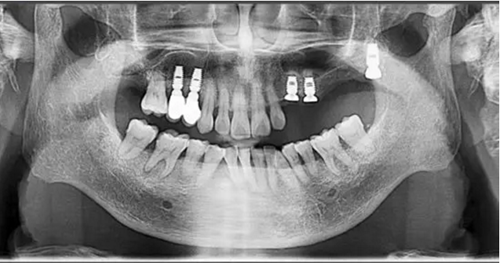

術后當天 術后7個月

術后8個月 術后10個月

術后13個月

術后14個月